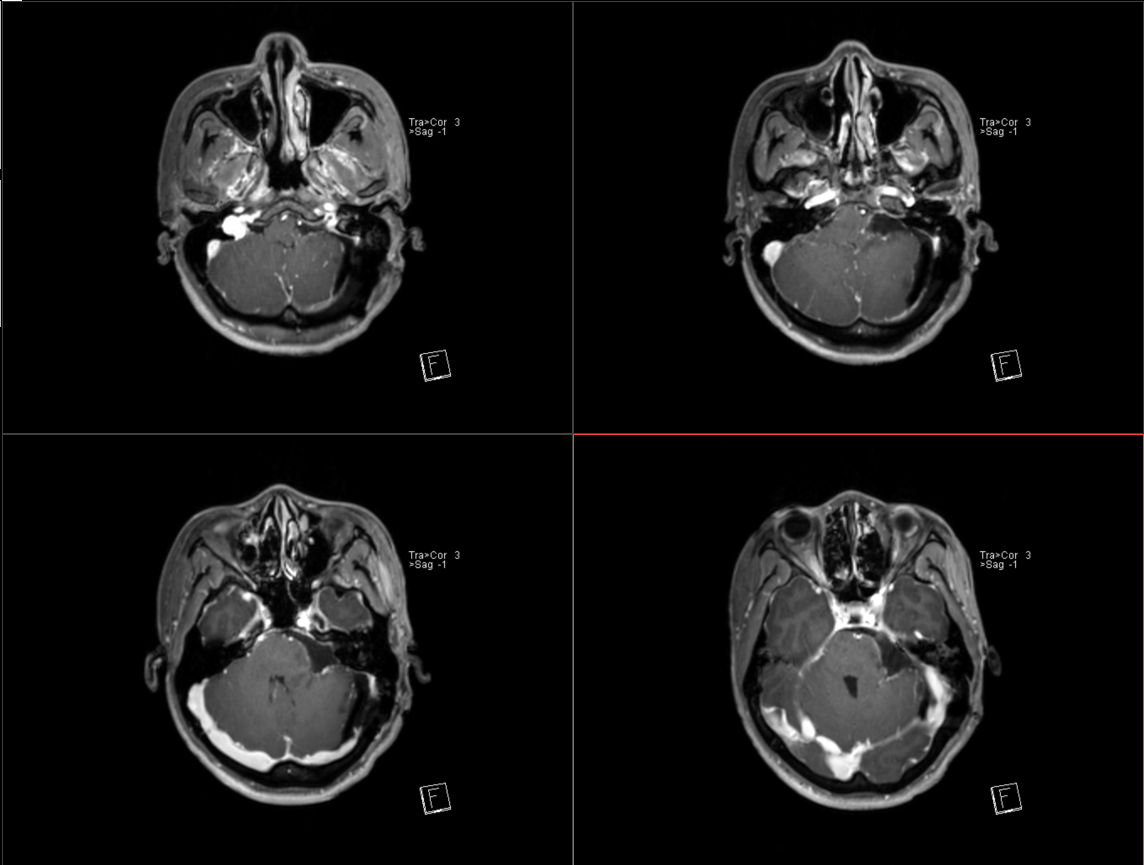

术后影像: